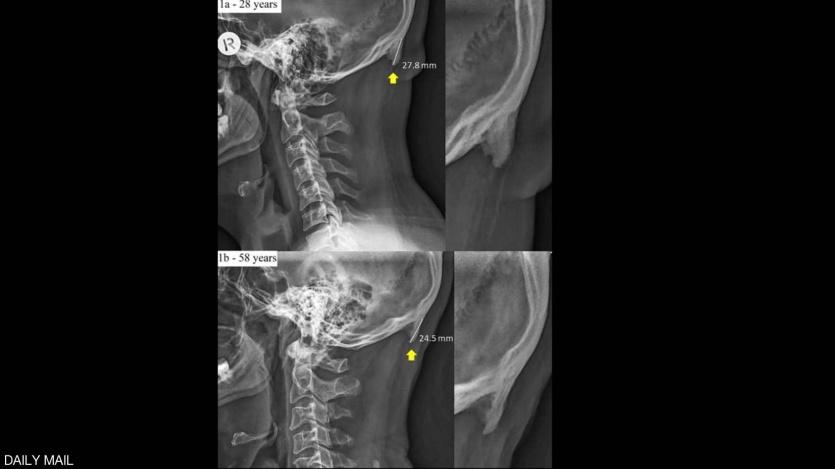

وبحسب ما نقلت صحيفة "ديلي ميل" البريطانية، فإن الشخص الذي يكثر من استخدام الهاتف الذكي، يظهر لديه ما يشبه شوكة عظمية في الجهة الخلفية من جمجمة الرأس، بسبب الانحناء والتركيز في شاشة الجهاز.

وتوضح الدراسة التي جرى إعدادها في جامعة "سان شان كوست" الأسترالية، أن جمجمة الإنسان أضحت تحدث هذه "الشوكة العظمية" بشكل متزايد.